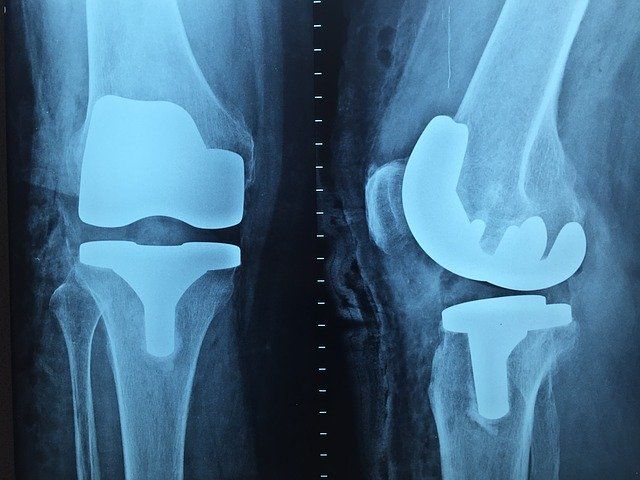

Implantar una prótesis es una complicada operación que exige buenos especialistas. Igual de fundamental es la profesionalidad de ellos como el nivel de calidad de la prótesis que se implantará, pudiéndose así evitar cualquier tipo de riesgo y que su adaptación sea la mejor posible.